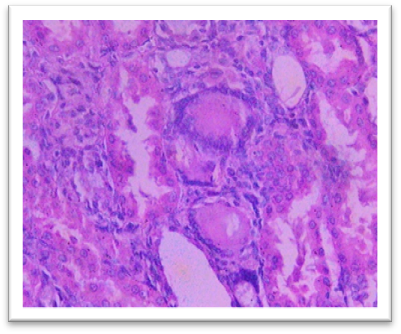

Histopathology

On day 42, rats were sacrificed for histopathological examination. Group I (Normal) and Group II (Lanthanum Carbonate only) showed normal kidney and liver architecture. Group III (Chronic Kidney Disease control) exhibited kidney damage, including crystals, congestion, haemorrhage, interstitial nephritis, and tubular dilatation. Group IV (Lanthanum Carbonate @150 mg/kg) showed moderate kidney fibrosis, mononuclear infiltration, and crystals. Group V (Lanthanum Carbonate @250 mg/kg) had mild fibrosis and sparse crystals. Group VI (Lanthanum Carbonate @500 mg/kg) showed minimal fibrosis and negligible crystals. Group VII (Lanthanum Carbonate @750 mg/kg) had minimal lesions with no crystals. Liver sections were normal in all groups. Histopathology studies revealed , The kidneys from a Chronic Kidney Disease (CKD) control rat (Group III) displayed significant macroscopic changes, including an increase in overall kidney size and the presence of multifocal, pinpoint, white granular raised lesions that were widely dispersed across the cortical surface. These observations are consistent with pathological alterations associated with CKD. Similar findings were reported by Yang et al. (2013) and Ali et al. (2015), who observed renal tissues exhibiting varying degrees of swelling and the presence of widespread white granular deposits on the cortical surfaces, consistent with the pathological features described in this study. Damment et al. (2011) observed significant changes in kidney architecture of Adenine induced Chronic Kidney Disease animals. The kidney from Group VII, treated with Lanthanum Carbonate @ 150mg/kg, 250mg/kg , 500mg/kg and 750 mg/kg body weight, demonstrated significant architectural improvement, along with a notable reduction in the number of crystalline deposits, indicating a substantial restoration of renal morphology and potential therapeutic efficacy at this dosage.

Fig. 19 Group III Kidney exhibits the crystals, congestion and haemorrhage. interstitial infiltration of mononuclear cells and fibrosis. Dilatation of the tubules, focal oedema, and focal interstitial nephritis under H & E 400X.